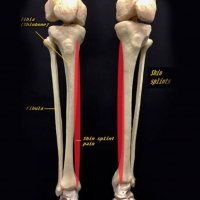

MEDIAL TIBIAL STRESS SYNDROME (MTSS)

Medial tibial stress syndrome (MTSS), also known as shin splints, describes a spectrum of stress injury that occurs at the medial tibia. This term is often used to indicate any type of tibial stress injury or the earlier manifestations of a tibial stress lesion before a fracture component can be identified. It is considered a low risk stress fracture.

Shin splints are a common exercise-related problem. Typically occurs in athletes (e.g. runners/jumpers) and is characterized by localized pain that occurs during exercise at the medial surface of the distal two-thirds of the tibial shaft, where muscles attach to the bone. Shin splints often occur after sudden changes in physical activity. These can be changes in frequency, duration and intensity.